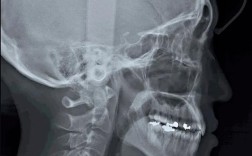

| 头颅侧位片 | 分析颅面骨骼的形态、位置关系(如SNA角、SNB角、ANB角),评估面部软组织轮廓,判断骨性畸形类型 | 骨性错颌畸形诊断,制定拔牙方案,预测矫正后面型变化 |